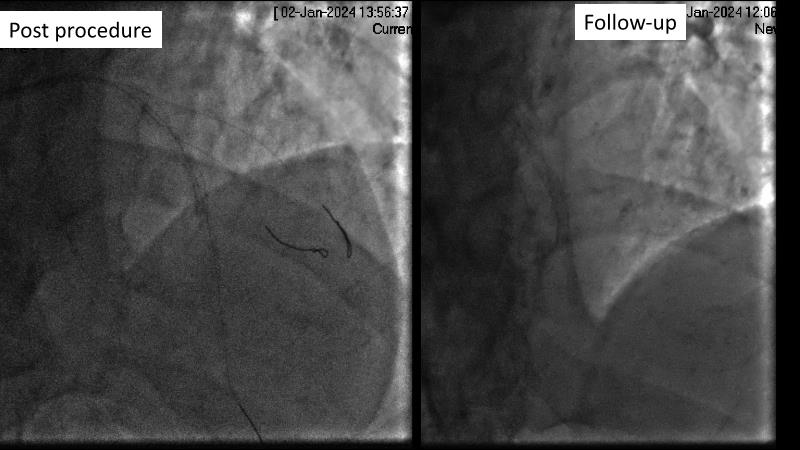

Browse this EuroPCR 2024 session to explore the safety and efficacy of sirolimus-coated balloons from pre-clinical data, review MagicTouch data from real-world populations with case-based examples, and learn about the MagicTouch sirolimus-coated balloon clinical programs. Discover insights and takeaways from the significance of the EASTBOURNE subgroups, and analyze the challenges and opportunities in PCI for diabetic patients.

- To learn from the real world registries and complex cases to understand the practical implications and potential of the device in diverse patient population